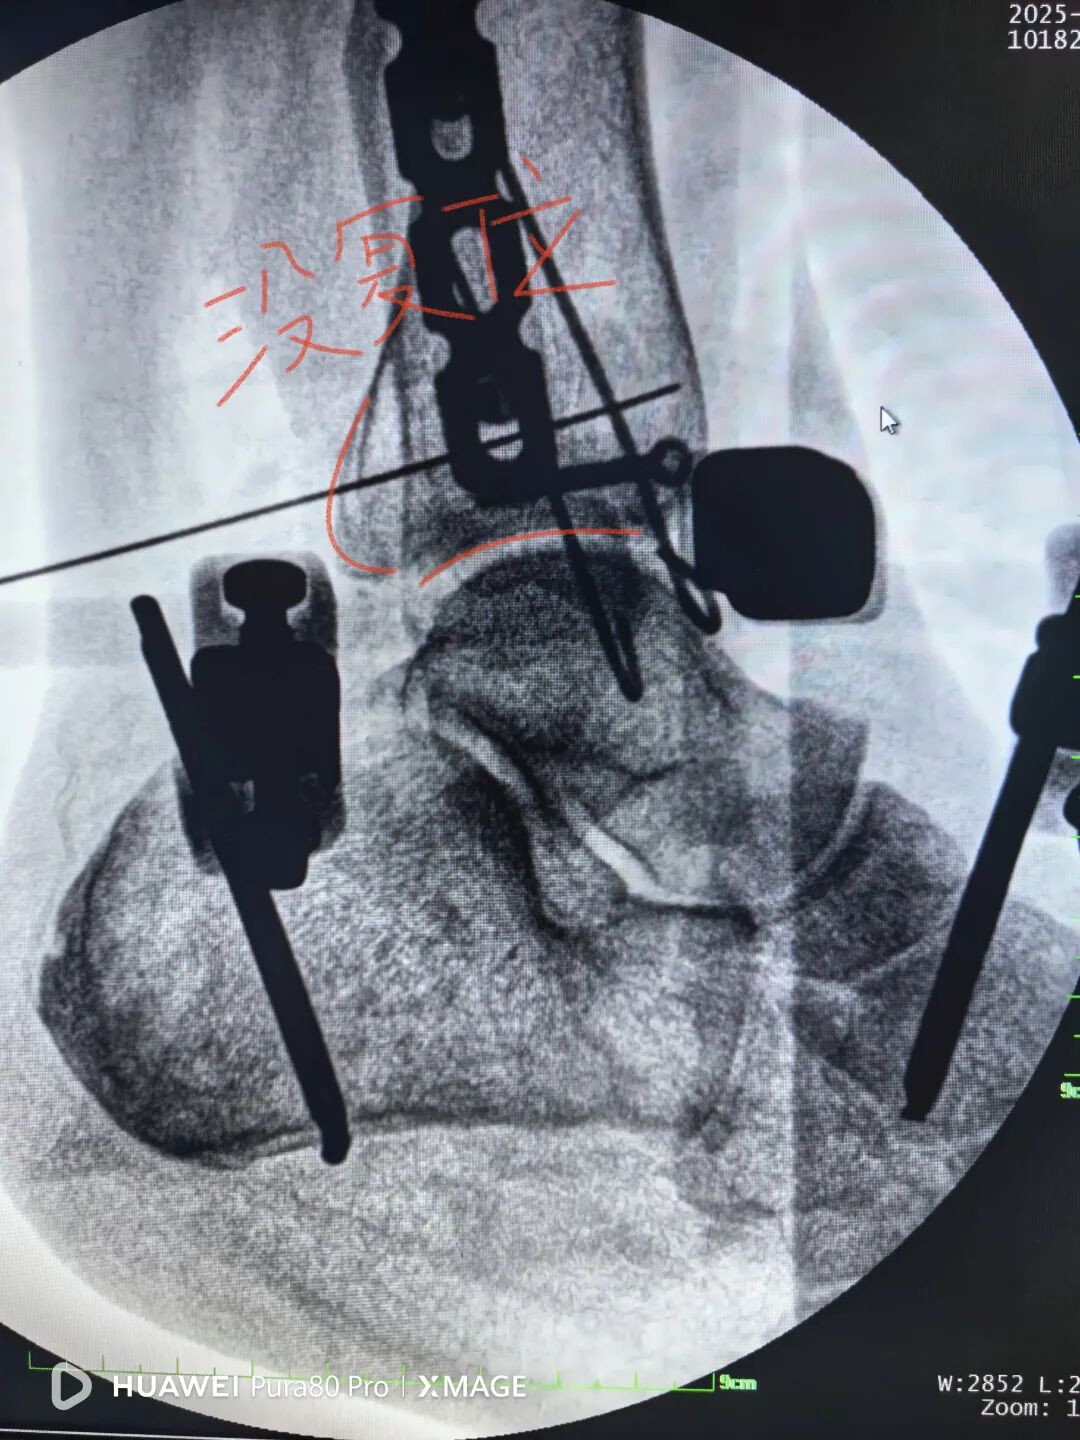

没有松外架

骨折没复位

松外架后,保持踝关节中立位

依靠软组织铰链复位后踝